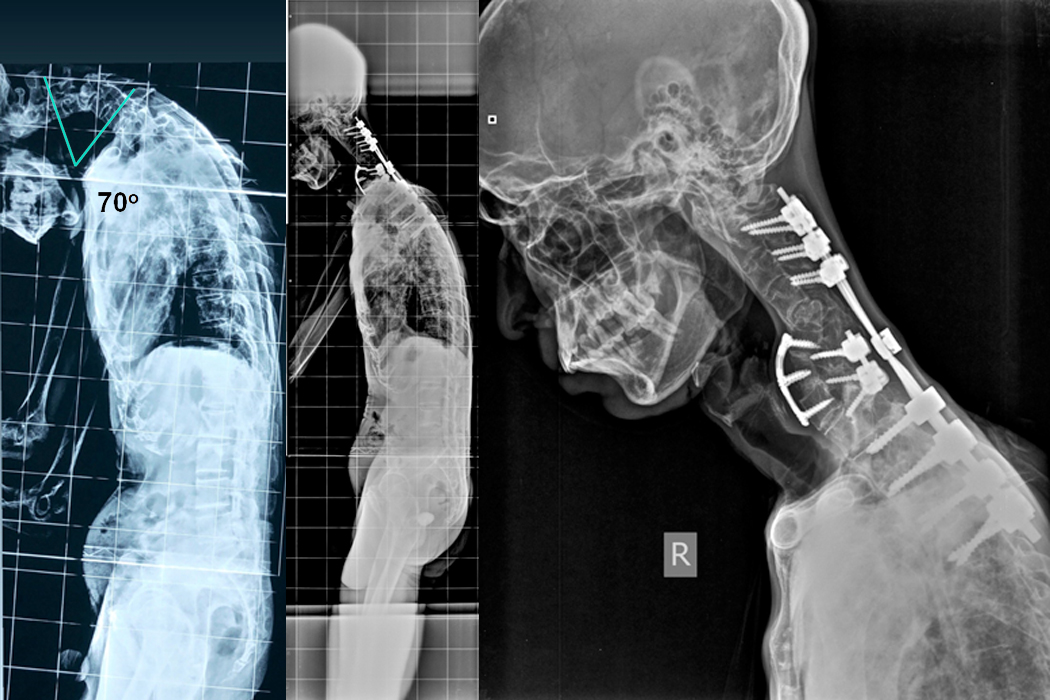

Patient D

A 46 year old male presented with progressive deformity of the neck (Chin-on-chest deformity) for last 6 months after lifting heavy weight on head, weakness of all 4 limbs with gait instability and urinary problems for which he was catheterised since 2 months. He was initially put on Halo gravity traction and then Combined Anterior and Posterior fixation with decompression and Deformity correction was done on 23.07.2019.

Hover over the image to view Pre & Post-op X-Rays